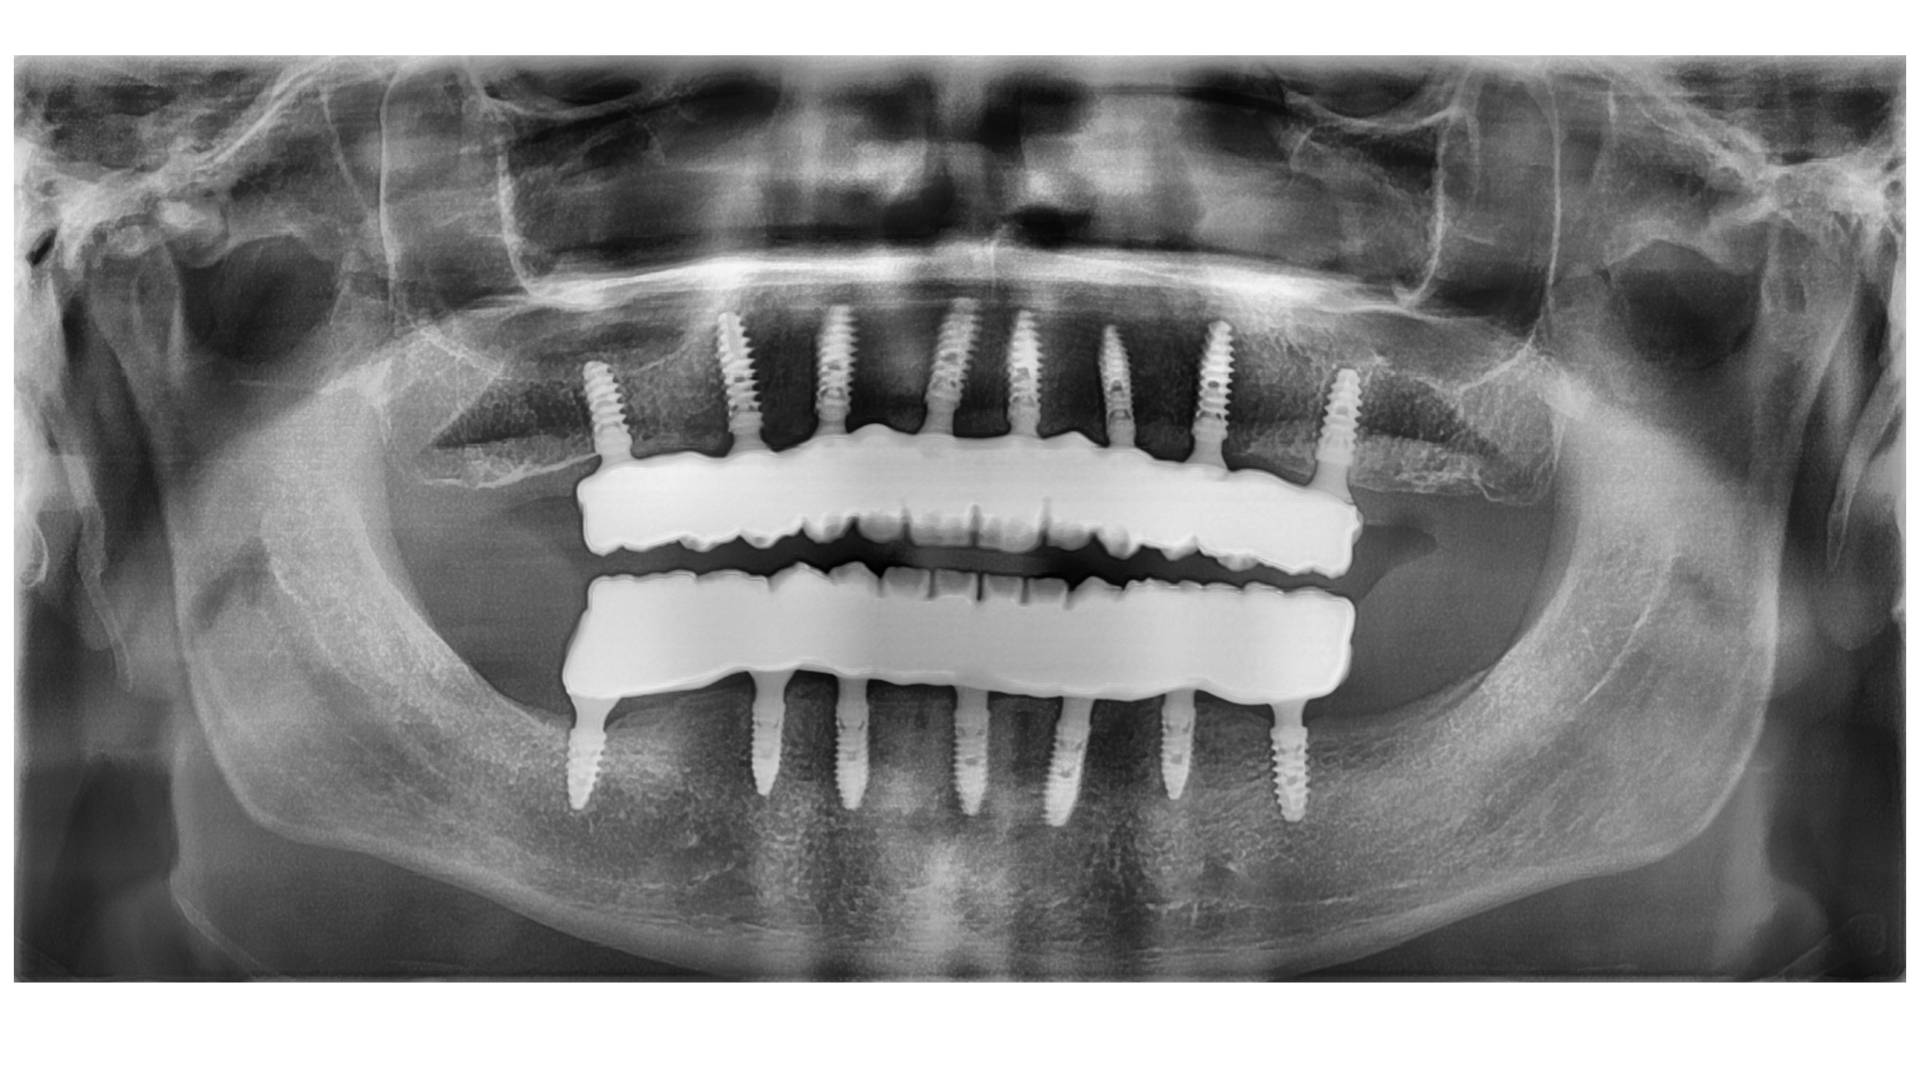

Después de un análisis completo y de revisar su Tomografía Axial Computarizada (TAC), propuse extraer todos los dientes existentes y colocar implantes el mismo día, También le ofrecí la posibilidad de tener dientes fijos el mismo día de la cirugía, lo que se conoce como carga inmediata de los implantes con una prótesis híbrida provisional, en caso de que la estabilidad de los implantes fuera buena.

Paciente siempre había tenido mucho miedo al dentista, por lo que le propusimos proceder con la cirugía bajo sedación consciente, para que el paciente estuviera tranquilo y no recordara nada después de despertarse de la cirugía. El paciente aceptó, así que realicé la cirugía con anestesia y sedación consciente, y la cirugía salió muy bien, lo que nos permitió tomar medidas el mismo día y hacer una carga inmediata, evitando que el paciente estuviera sin dientes en ningún momento. Una vez que los implantes se habían cicatrizado, tomamos medidas para la prótesis definitiva, que en este caso fue hecha de circonio. El paciente está feliz con su sonrisa, pero sobre todo comenta que ahora puede comer con alegría.